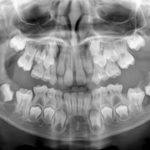

Cisti eruttive multiple in un bambino di 7 anni. Caso clinico